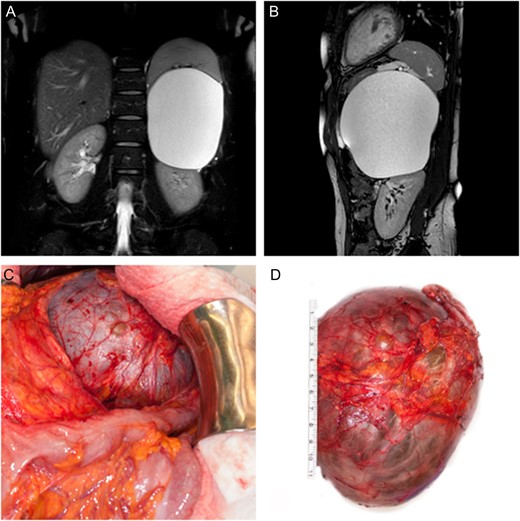

On physical examination, the patient had normal vital signs. Her abdomen was soft, non-tender and non-distended. Laboratory investigations showed a slightly elevated white blood cell count as well as C-reactive protein level. Beta-HCG test was negative. Computed tomography scanning of the pulmonary arteries was performed in order to rule out pulmonary embolism. The simultaneous display of the upper abdomen revealed a big cystic lesion, which seemed to be attached to the left kidney. Biochemical analysis and hormone testing showed no signs of a hyper functioning mass. Abdominal MRI revealed a maximum diameter of 12.5 cm. The origin of the cystic lesion was suspected either in the mesentery or the omentum majus (Fig. 1A and B). Considering the abdominal symptoms as well as the fact that neither origin nor dignity could be determined in this patient, a total surgical removal followed by histological examination was indicated.

(A, B) Coronal and sagittal T2 weighted, fat suppressed MR image of the abdomen showing displacement of the spleen as well as the left kidney by the adrenal tumor. (C) Intra-operative finding showing close proximity of the cystic lesion to the left colonic flexure. (D) Surgically excised cystic tumor together with the left adrenal gland.